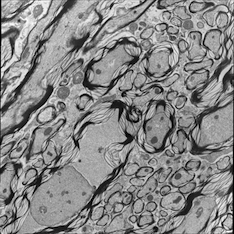

5.3.2 Image Analogies Results

We tested the original image analogy method and our proposed method on correlative microscopy images. For each test dataset, I train the dictionaries based on two randomly selected image pairs. We can also train the dictionaries based on more datasets at increased computational cost. In both image analogies methods I use 15×15151515\times 15 patches, and in our proposed method I randomly sample 100001000010000 patches and learn 900900900 dictionary elements in the dictionary learning phase. We choose γ=0.01𝛾0.01\gamma=0.01 and λ=1𝜆1\lambda=1 in (7). The learned dictionaries for both TEM and confocal images are displayed in Fig. 6. The image analogies results in Fig. 7 show that our proposed method preserves more local coherence than the original image analogies method.

Refer to caption

(a) case 1: TEM image

(b) Registered confocal image

(c) Original IA result

(d) Proposed IA result

(e) case 2: TEM image

(f) Registered confocal image

(g) Original IA result

(h) Proposed IA result

Figure 7: Result of Image Analogies (IA)